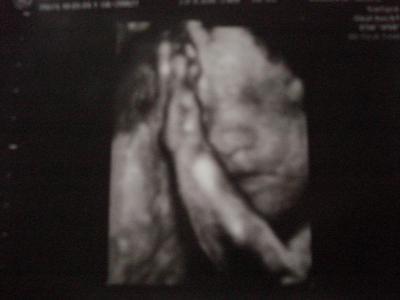

Hallöchen, alles super!!!! Der Kleine wiegt ca 1200 g und ist ca. 38 cm groß. Muss jetzt den Großen vom Kiga abholen. Hier noch schnell ein Bildchen :o) lg julia

Bild zu Heute VU - Forum für Juli - Mamis

Na der ist ja süß. Da fühlt sich aber einer pudelwohl... und verkuschelt ist er ja auch noch!!! LG Julia

Sieht wirklich süüüüüüüüß aus!!! Als wollte er Dich streicheln :-)